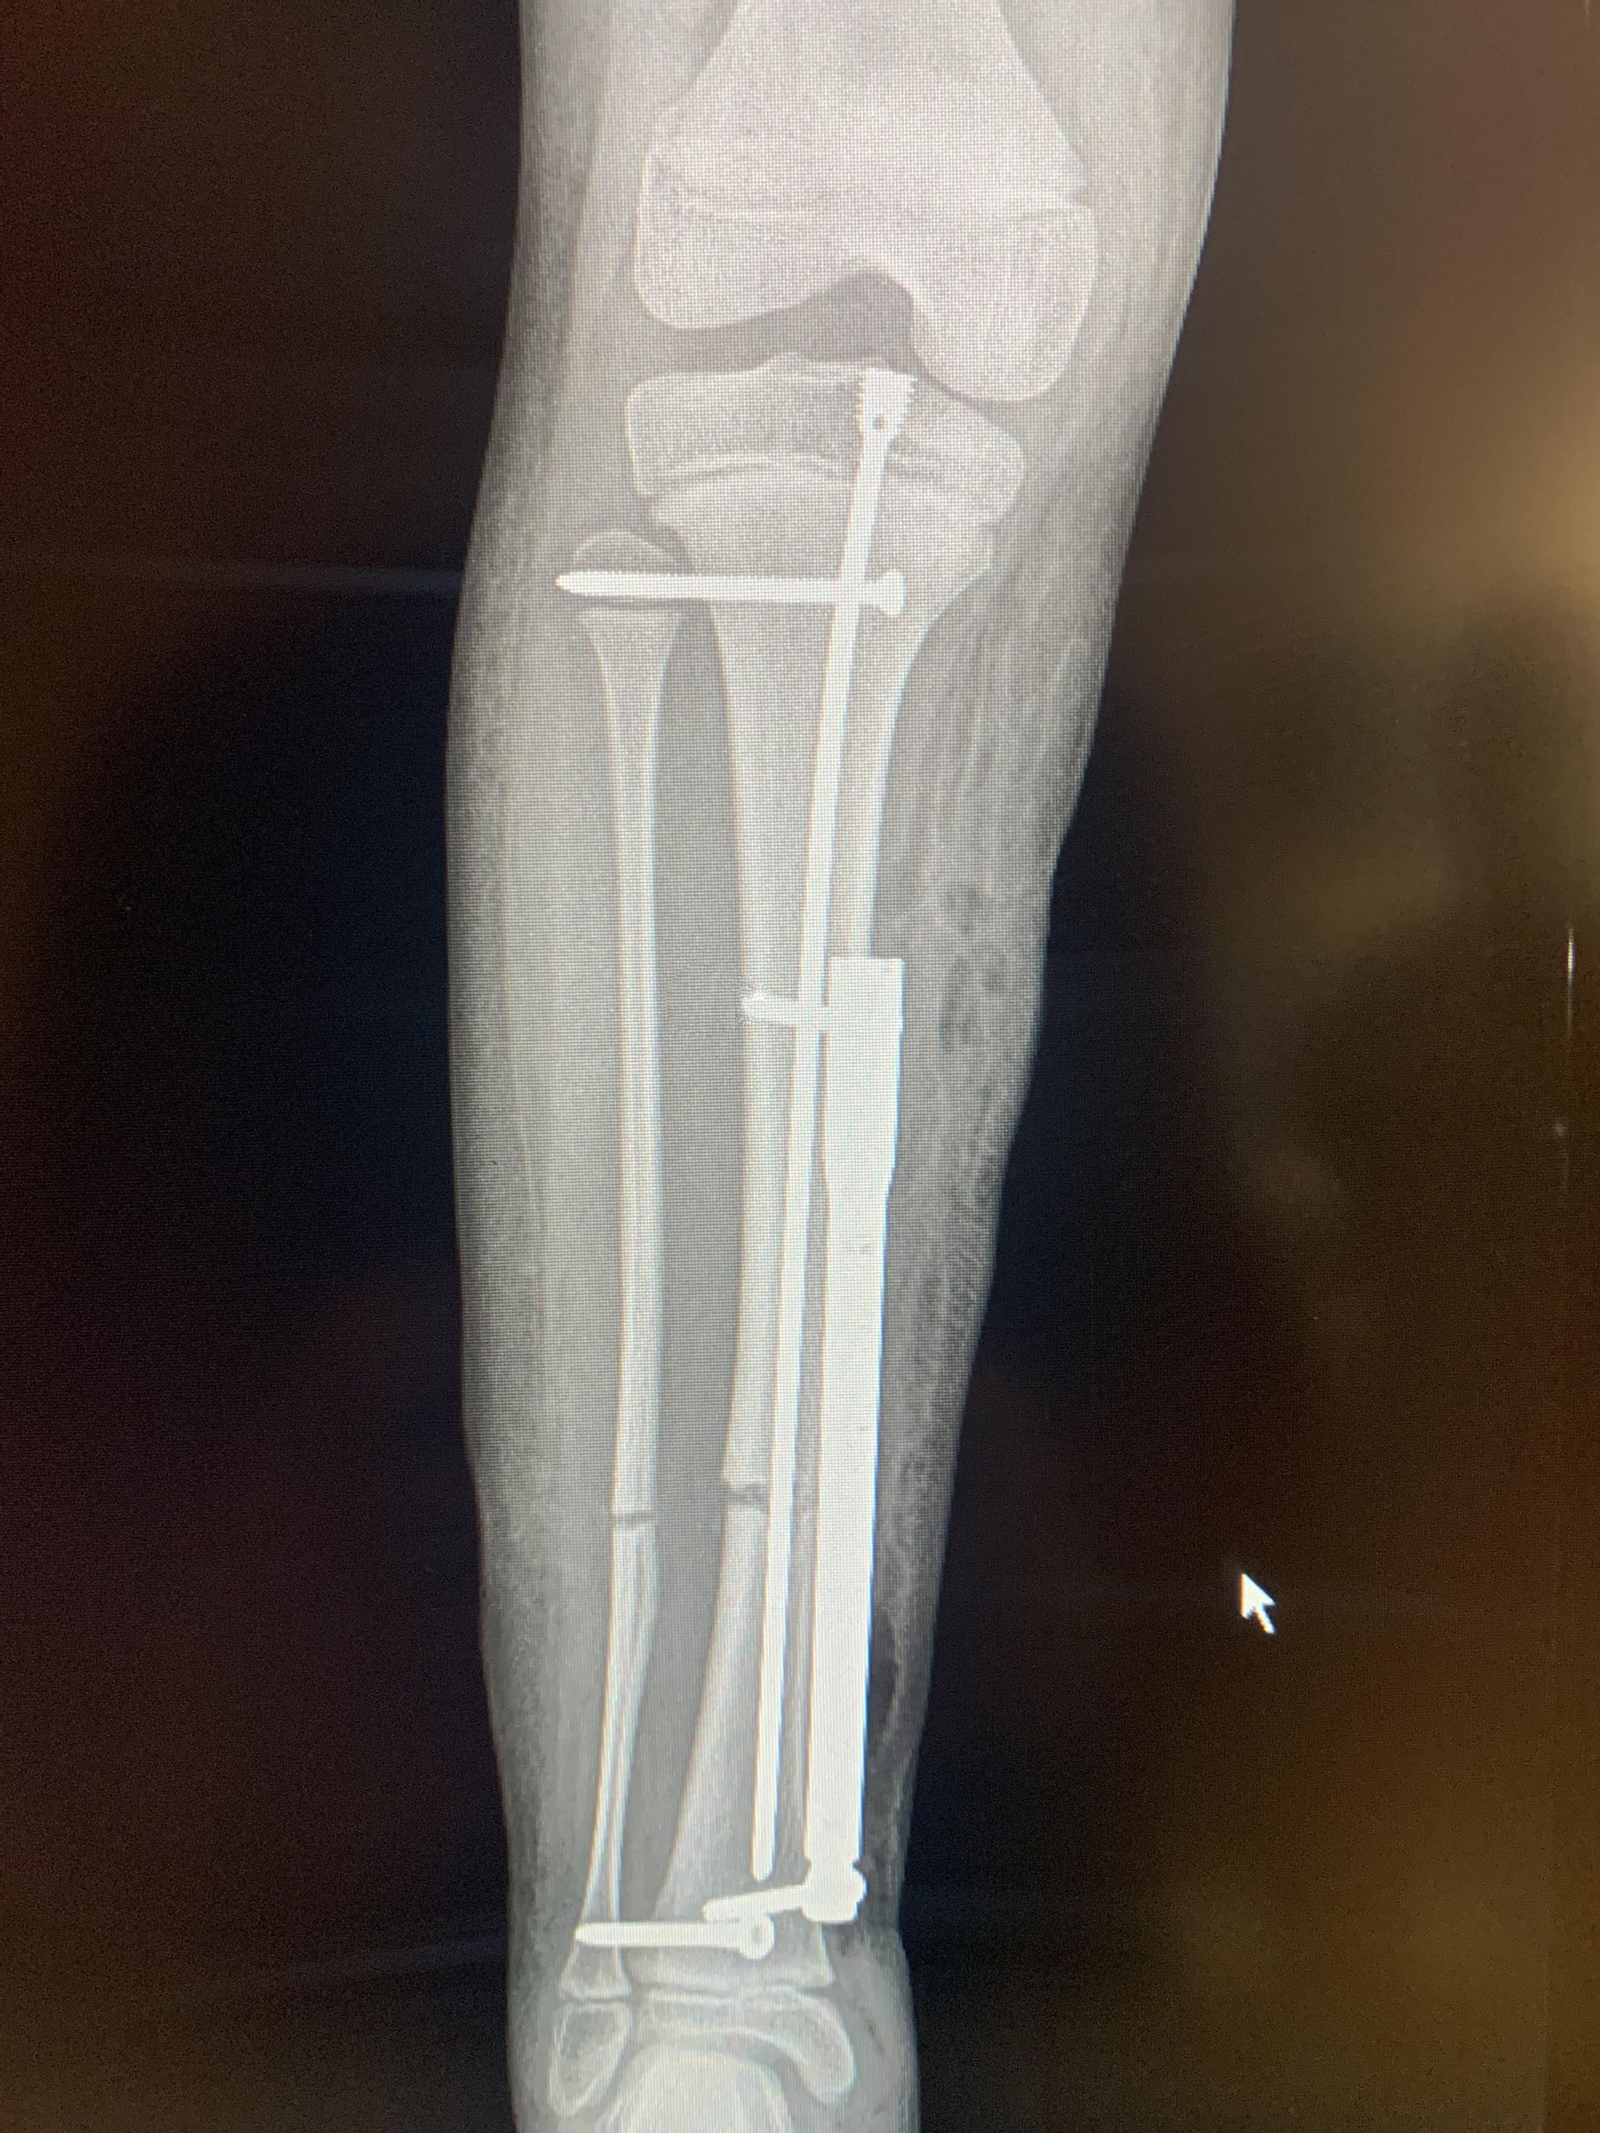

La imagen muestra el dispositivo de alargamiento del hueso.

La imagen muestra el dispositivo de alargamiento del hueso. / R. D.

La intervención ha consistido en colocar un dispositivo por vía subcutánea para lograr alargar la tibia a través de ondas electromagnéticas. Se trata de un paso más en el campo de la cirugía ortopédica infantil para corregir discrepancias entre las piernas, sin afectar al normal crecimiento de la menor.

Otra opción es interna: “El dispositivo interno de alargamiento electromecánico es activado por un imán. A través de este imán un clavo ubicado en el interior del hueso recibe ondas electromagnéticas emitidas desde el exterior, que estimula el clavo y lo alarga”, añade.

El clavo colocado en el hueso tiene una serie de engranajes que hacen que se alargue al ritmo elegido por el especialista. Esta opción de colocar el dispositivo de manera interna supone grandes beneficios al evitar heridas y el impacto emocional; pero resulta inviable en el caso de los niños porque interfiere en el crecimiento normal del hueso.

Ante esta tesitura, el doctor Downey ha diseñado una tercera opción y abre de este modo un nuevo camino para los casos pediátricos. “Se trata de una técnica que aprendí en EEUU, y consiste en colocar el clavo vía subcutánea o submuscular, pero no dentro del hueso, de modo que no daña la placa de crecimiento. Salvamos dos complicaciones: al no utilizar dispositivo externo (infecciones, cicatrices, etcétera) y evitamos provocar otros daños médicos al no colocar el clavo dentro del hueso”.

Después “abrimos la piel e insertamos el clavo por debajo de la piel”, describe el doctor Downey. Se coloca un tutor interno en la tibia y una vez colocado el clavo de manera subcutánea el siguiente paso en el quirófano es anclarlo a la tibia con unos tornillos.

“Se coloca un clavo liso dentro de la tibia, que es específico para no causar daño en la placa de crecimiento y, antes de terminar de introducirlo, se corta la tibia. Se coloca el clavo a lo largo de toda la tibia”. El siguiente paso consiste en abrir una herida a nivel del tobillo. “Se introduce el clavo de alargamiento por debajo de la piel y se ancla a la tibia con dos tornillos”, añade. Se cierran todas la heridas y se comprueba en quirófano que el clavo funciona correctamente.